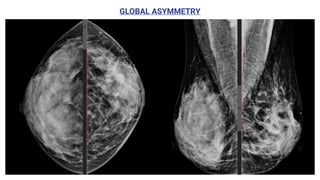

● Global asymmetry consisting of an asymmetry

over at least one quarter of the breast

Is usually a normal variant.

GLOBAL ASYMMETRY

• #18 This is an example of global asymmetry in the breast. The entire right breast is denser than the opposite breast. This finding has been present and stable for 4 years. No evidence of solid nodules in the ultrasound study (not shown), only simple mammary cysts were visualised bilaterally, compatible with BI-RADS II (benign findings).